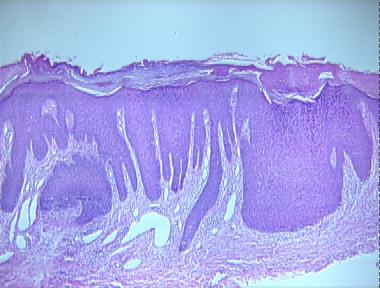

prurigo nodularis

Histologic Features